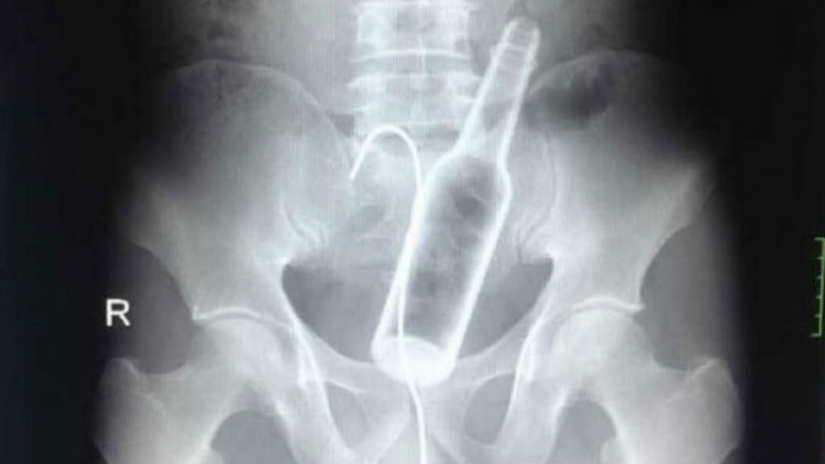

Uno de los hospitales Chinos, vino un hombre con quejas de dolor abdominal. Los médicos tomaron una radiografía y se encontró una botella de vidrio en el estómago.